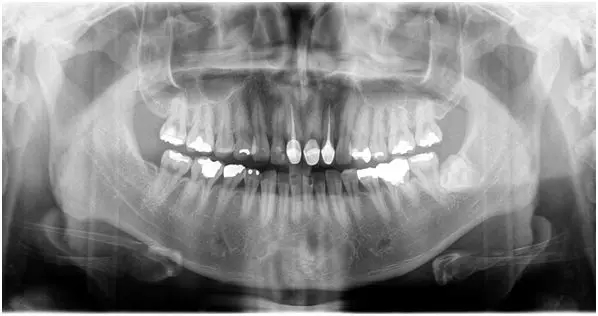

通過(guò)獨(dú)立的CMOS探測(cè)器直接進(jìn)行二維全景片的拍攝,圖像質(zhì)量好,免去拆卸的的麻煩。一板多用,簡(jiǎn)單方便。